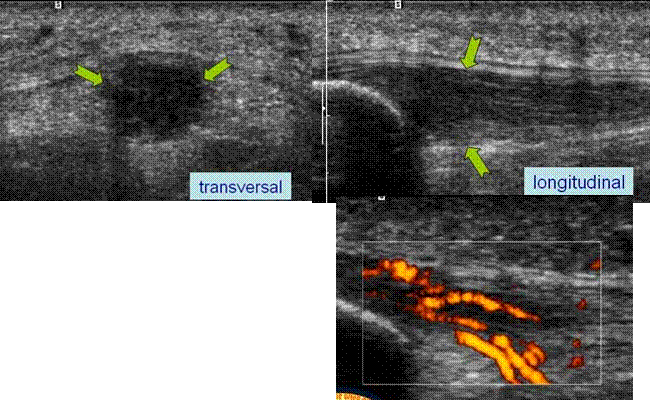

CHIST SINOVIAL COMPRESIV

Dureri cronice pe fata interna a gleznei cu parestezii

pe marginea interna a piciorului

Formatiune chistica cloazonata ingloband si comprimand

Nervul plantar extern →

Tendonul flexorului propriu al halucelui →

Confirmare IRM